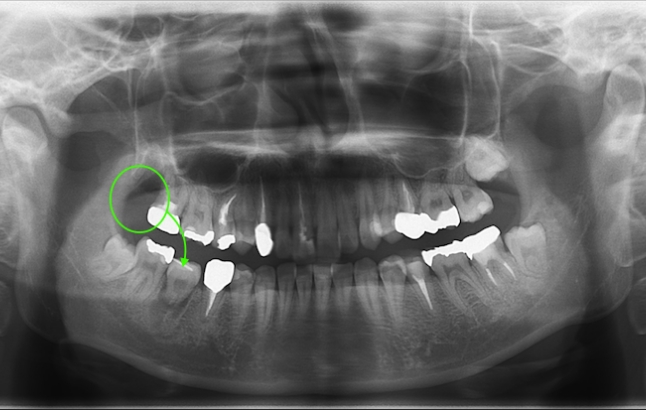

以下の写真の患者様は、移植した歯の歯根根の成長がまだ終わっていなかったため、歯を削ったり神経を取ったりすることなく、移植から11年経った現在も、そのままの状態で自分の歯として元気に機能しています。

当院では5〜10年をひとつの節目とし、炎症・咬合・審美の安定を総合的に評価。

骨量が少ない症例でも、適切な診断と手技によって高い生着率を維持しています。